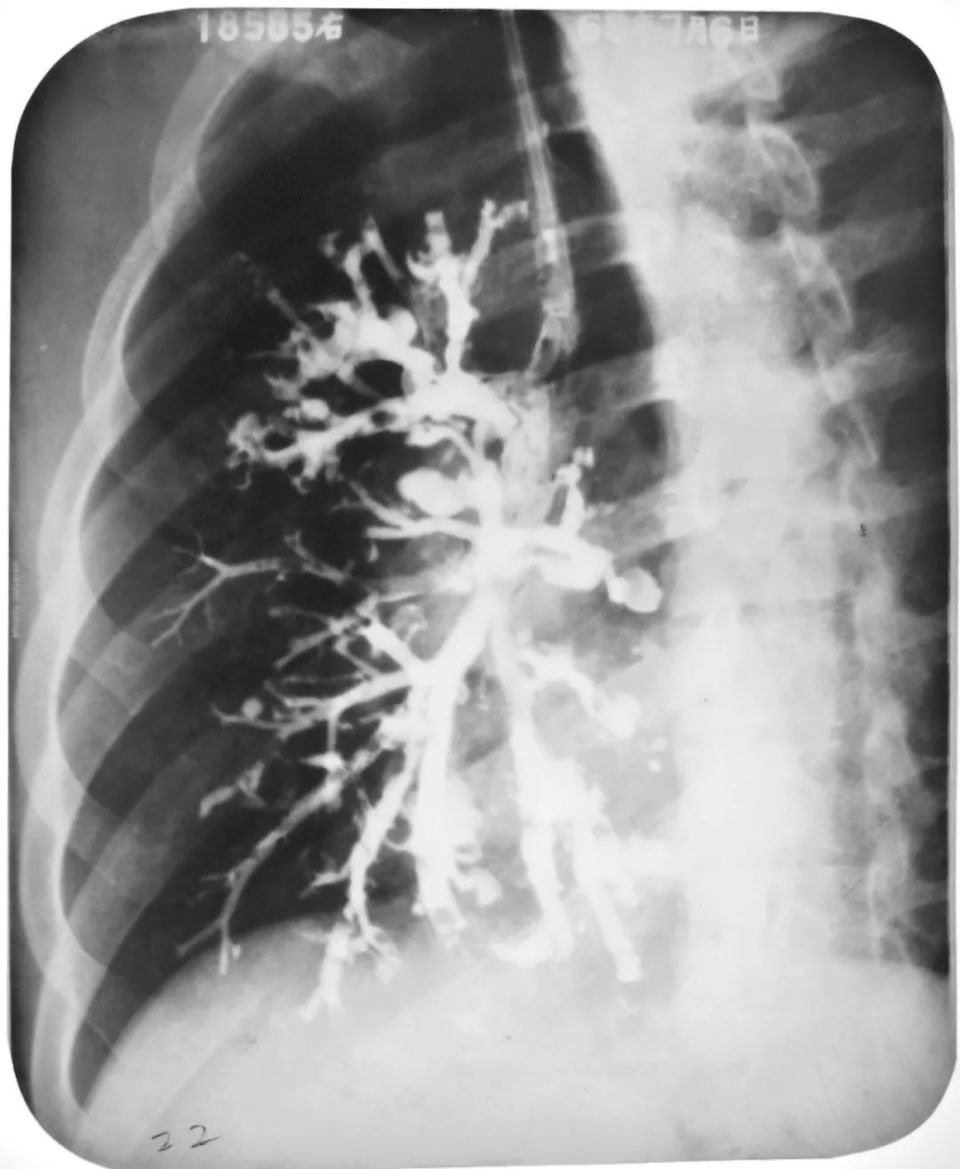

左下叶支气管扩张

左下叶支气管囊状、柱状扩张

右肺支气管扩张

右肺支气管呈囊状、柱状扩张